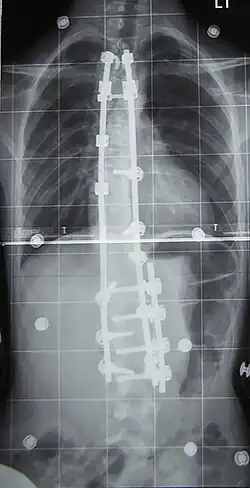

Spondylodeza – zrośnięcie się dwóch lub więcej kręgów (wytworzenie bloku kostnego) jako objaw uboczny w wyniku czynników patologicznych lub zamierzony wynik operacyjnej stabilizacji. Operacyjne wykonanie spondylodezy ma na celu wyeliminowanie ruchomości segmentalnej w celu wyeliminowania przyczyn objawów klinicznych, a także zatrzymania postępu deformacji, a w miarę możliwości jej korekcji.